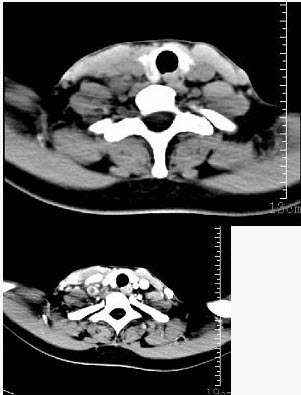

女性35岁,发热、盗汗近3个月,颈部摸到多个结节,CT扫描如图所示,请选择最可能的诊断()。

A:神经鞘瘤

B:结节病

C:淋巴转移癌

D:淋巴结核

E:淋巴瘤